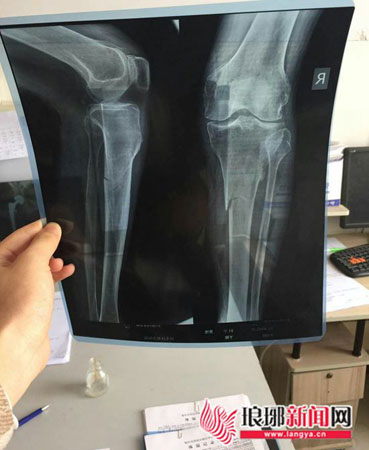

X线片显示老人的小腿骨折

据老人回忆,不法分子对他的腿部和头部均进行了殴打。目前,老人正在医院做进一步检查。“老人很和善,与邻居关系也都不错;他是村里的五保户,无经济、产权纠纷。你说这些人怎么这么丧良心,打一个90多岁的老人!”想到年迈的姥爷遭遇殴打,褚先生十分难过。